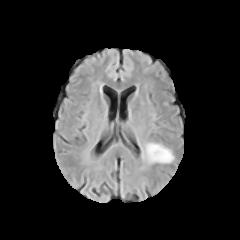

Refer to caption

(a) Healthy scan

(b) Scan presenting a tumor

(c) Highlighted lesion of the ill brain

Figure 1: Examples of MRI scans available in the dataset

Figure 1 provides examples of images labeled as healthy and ill. More specifically, 0(b) is the image of the scan of a brain containing a tumor, which is found in its lower-right part as a white area that stands out from the rest of the organ; the latter is pointed in 0(c) in the highlighted red rectangle.